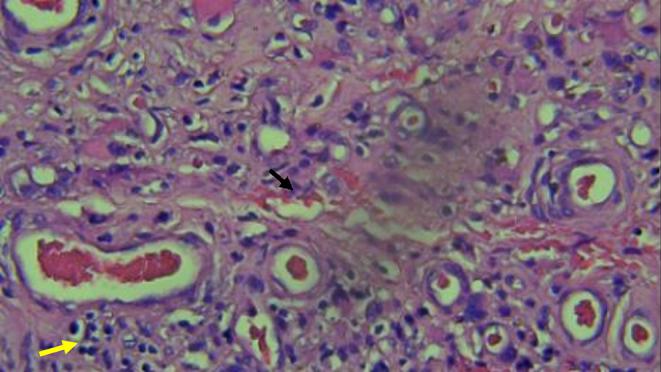

Diabetes foot ulcer (DFU) is a common long-term complication of diabetes. Intractable chronic wounds to standard care of diabetic foot raise the question of whether other factors intervene in disease development. We report a case of a 54-year-old male patient who came to Sardjito General Hospital with leg pain and previous history of multiple debridement and amputation for DFU referred from a remote hospital yet no improvement was evident in the surrounding lesion following treatment. Consequently, a histopathological examination was carried out proving the presence of other aetiologic factors, vasculitis and panniculitis existing in the lesion. In this case, we report a rare type of causative factor of foot ulcers among diabetic patients. Vasculitis suspected for polyarteritis nodosa accompanied by panniculitis is considered in this patient. The treatment of choice is corticosteroids or immunosuppressants based on the clinical condition, contrary to usual wound care in DFU. Based on the evidence, clinicians need to consider other causes than only macrovascular complications in a diabetic patient with DFU that is intractable to standard wound care. In this patient, vasculitis may be considered in forming diabetic foot ulcers alongside macrovascular complications.

LEARNING POINTS